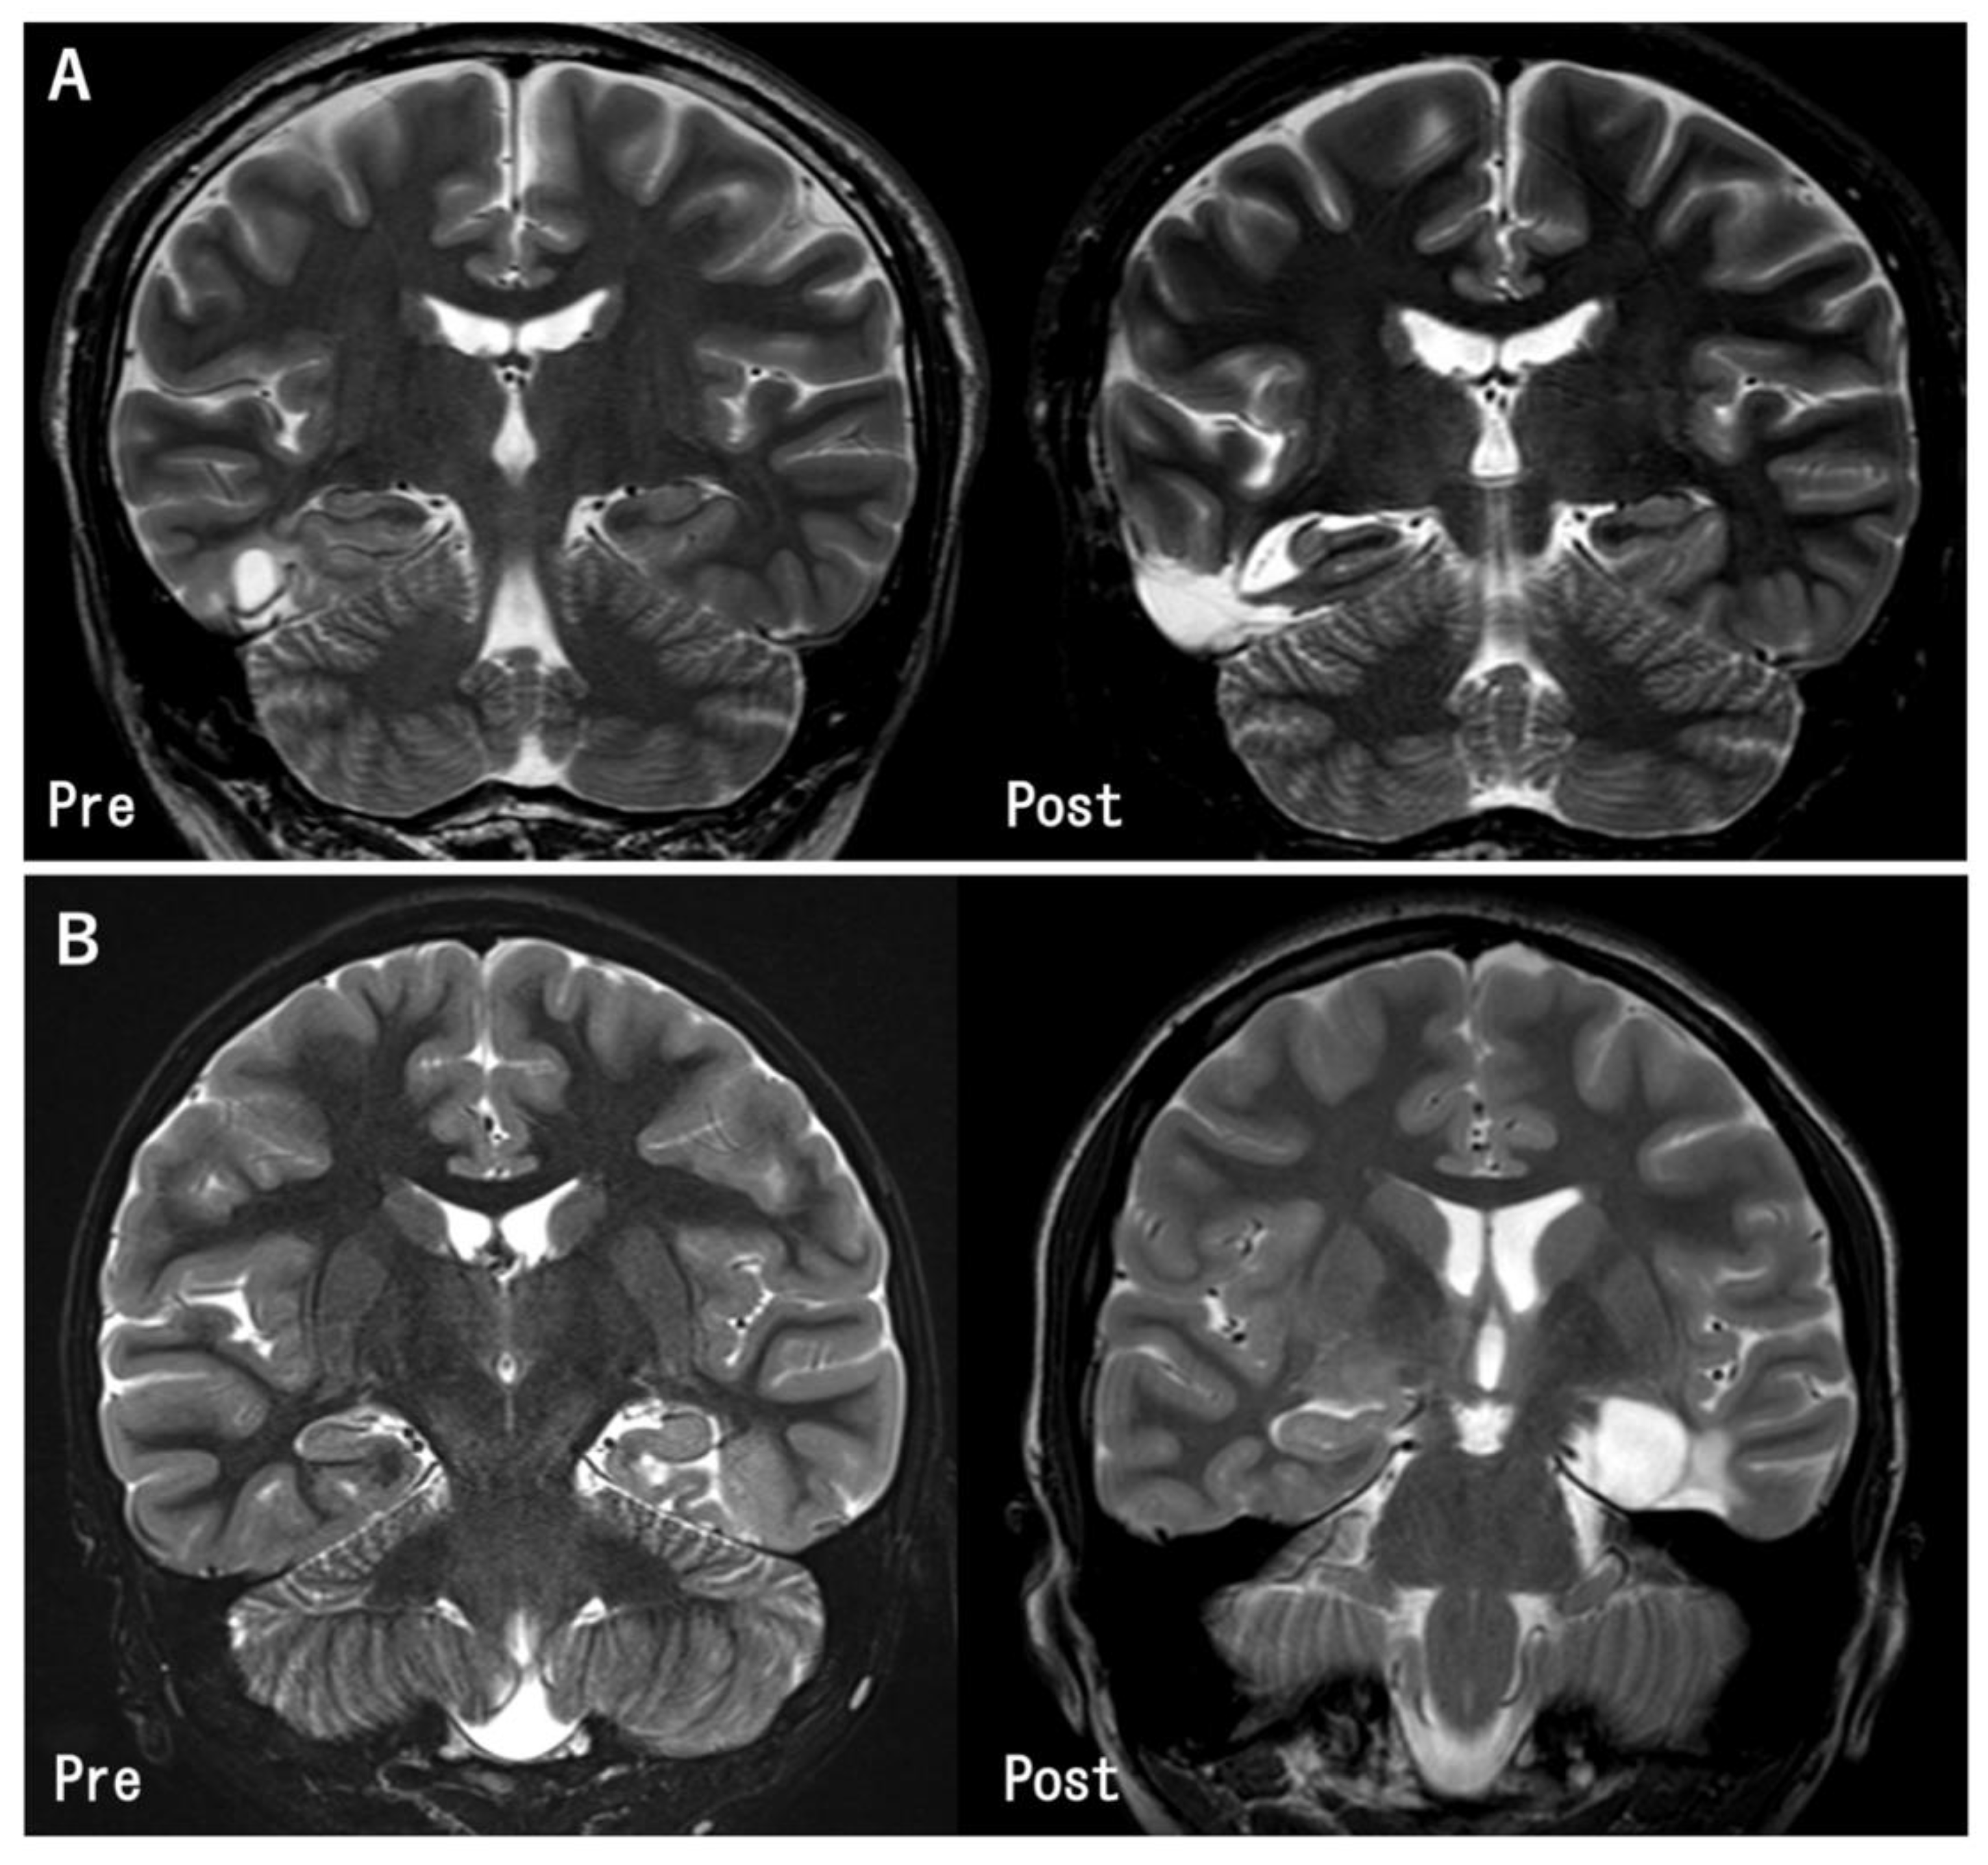

Figure 2.

Pre- and post-operative MR images in the representative cases. (A) The tumor in the inferior temporal gyrus was totally removed. The hippocampus was preserved because it was located apart from the tumor (Case 11). (B) The tumor was located at the left parahippocampal gyrus. Gross total tumor removal and hippocampectomy was performed (Case 27).